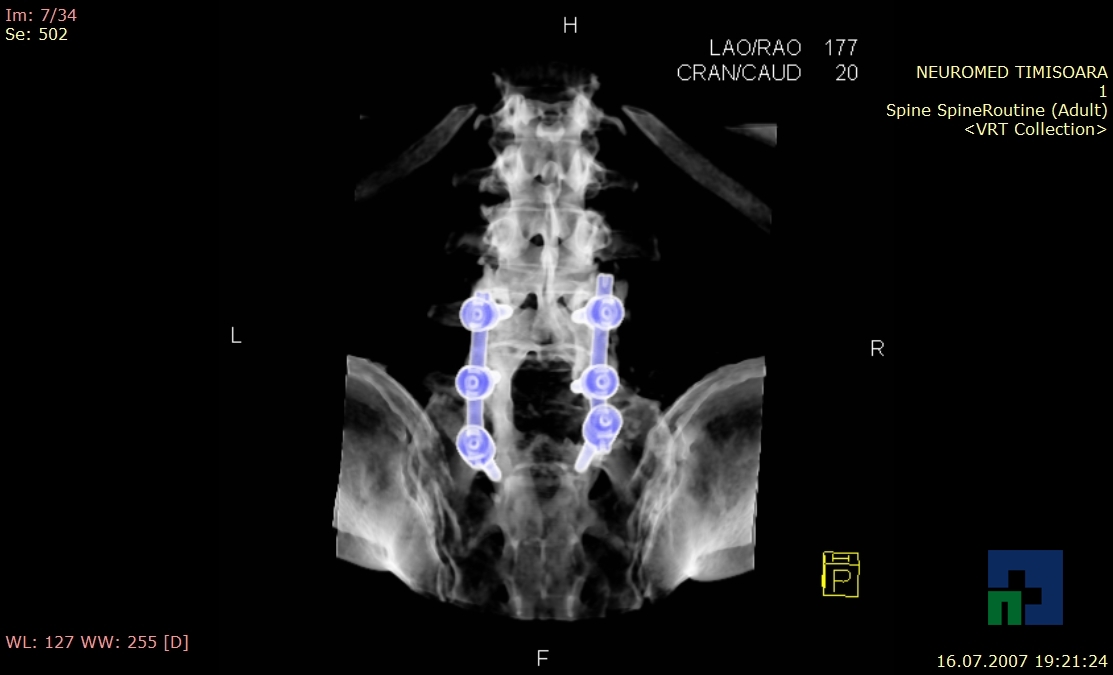

- Diagnosticul fracturilor:

-

- Unice

- Multiple

- Cu înfundare

- Complexe cranio-sinusale

- Complexe cranio-etmoidale

- Complexe cranio-orbitare

- Complexe cranio-faciale